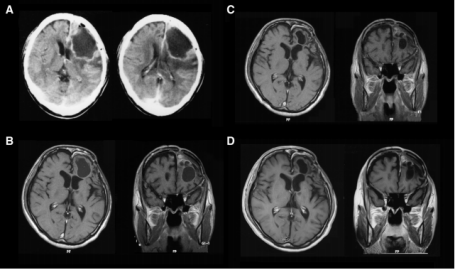

A 39-year-old man had received boron neutron capture therapy (BNCT) for a grade II astrocytoma (compatible with diffuse astrocytoma, not otherwise specified in the WHO 2016 criteria). He returned to his previous work after surgery, but, 7 years later, he suddenly developed seizures, and his health condition deteriorated.

Therefore, he underwent a second surgery. The mass removed in the second operation was mostly necrotic as a result of previous radiation treatment. He then showed no signs of recurrence and did not require any treatment other than antiepileptic drugs for 25 years. He was able to be employed by a listed company until the age of 65 years for light jobs as a physically handicapped individual. This case suggests the effectiveness of BNCT even for rather low-grade astrocytomas.